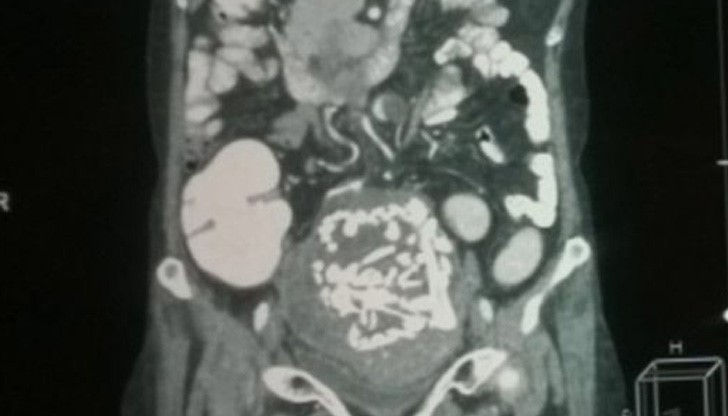

След години обаче болките се появили отново. При направения преглед специалистите открили подутина в долната дясна част на корема. Опасявали се, че става въпрос за раково заболяване. При изследванията открили калцирано образувание, в което на скенера видели скелет на ембрион.

Това е най-продължителната извънматочна бременност, регистрирана от медицинската наука до момента.